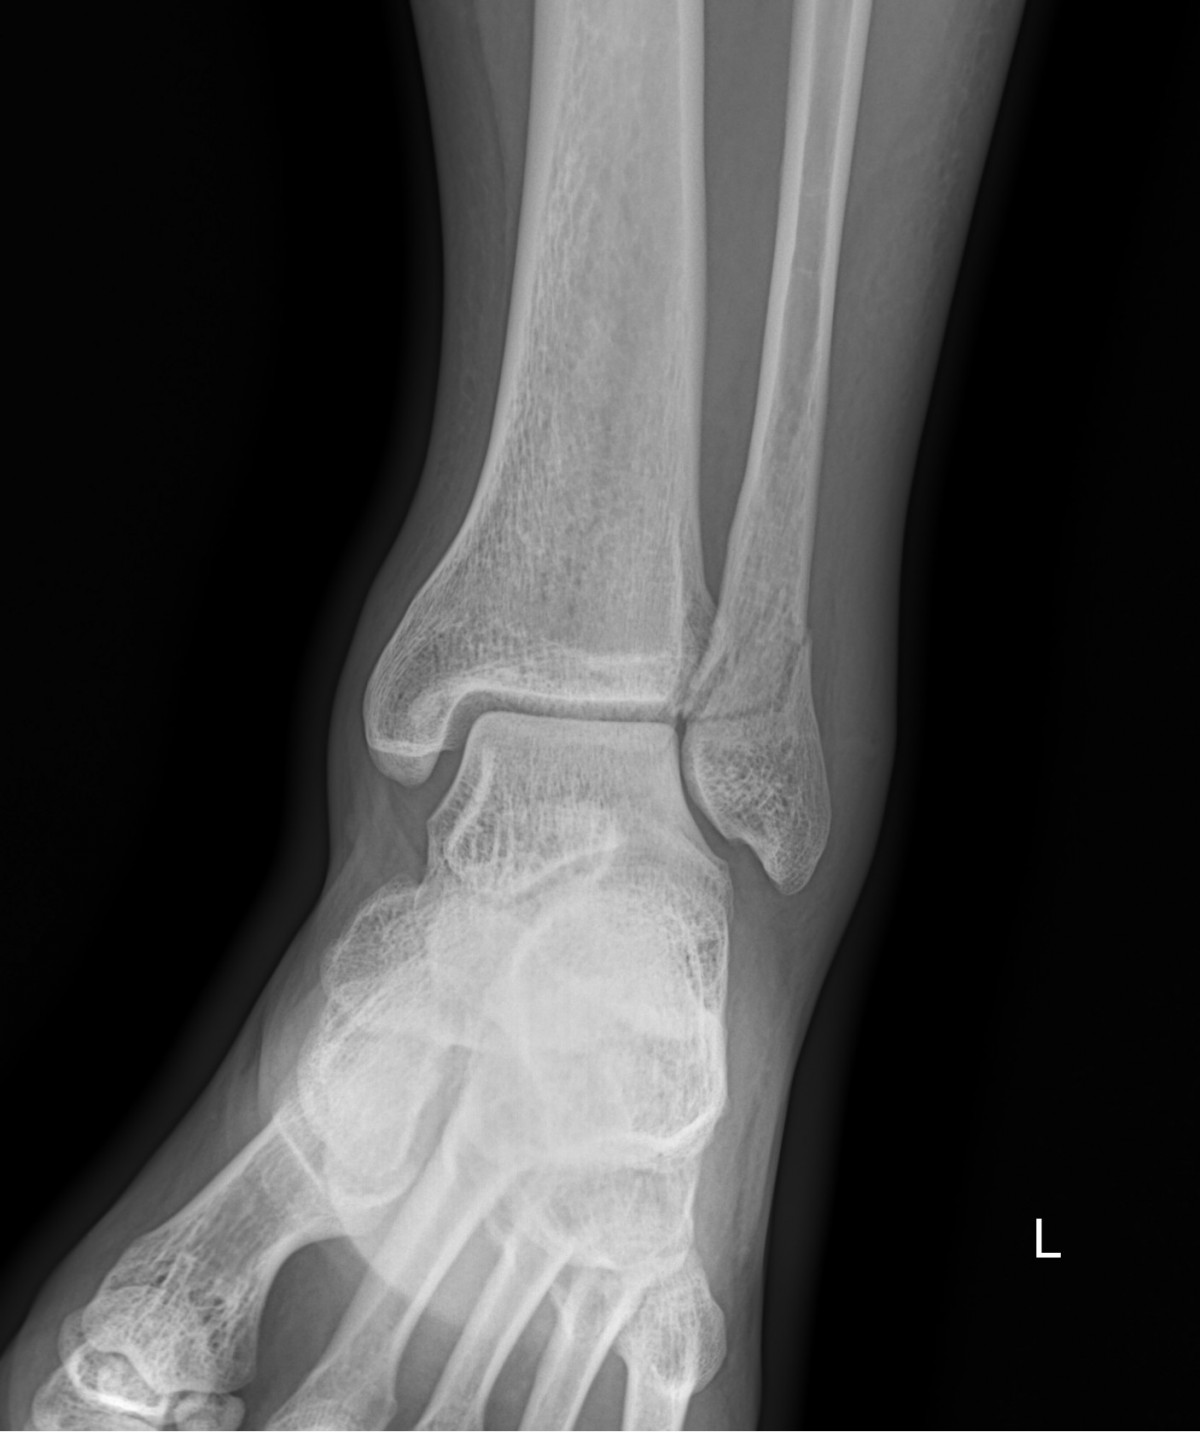

이재상원장님 발목 골절 수술 장용O 환자

dae765e4d9ac96aee867c9d6292d8784_1758002895_834.jpg